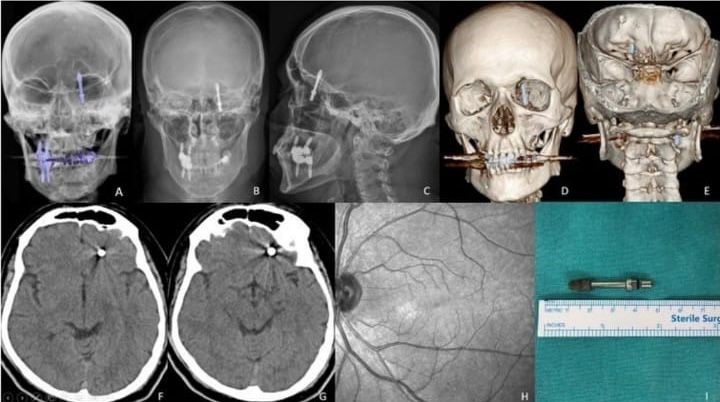

İddiaya göre, implantı çeneye yerleştirmek isteyen doktorun yanlış müdahalesi sonrası vida, Yılmaz’ın çene kemiğini delip kafatasına saplandı. Acı içinde kalan Yılmaz’ın yaşadığı baygınlık sonrası film çeken Doktor A.D., vidanın kafatasında olduğunu görünce hemen kendi aracıyla Yılmaz’ı bir hastaneye bıraktı. Hastanede çekilen tomografi sonrası gözlerine inanamayan doktorlar, 2 çocuk babası adamı hemen ameliyata aldılar. Saatlerce süren operasyon sonrası hayata tekrar dönen Yılmaz, günlerce taburcu olmayı bekledi. Sağlığına dönen Yılmaz, kendisine yanlış müdahale yapan diş hekimini aradığında ise ikinci bir şoku yaşadı. Yaptığı ödemenin iadesini isteyen Yılmaz’a doktor tarafından ret cevabı gelince Yılmaz, yargının yolunu tuttu.

Kendisini uyarmasına rağmen dinlemediğini ifade eden Yılmaz, “Daha sonra dişlerimi çekip, aynı gün implant uygulaması yaparken, işlemde kullandığı cihazın bozuk olduğunu sekreterine söyledi. Bu kez de işlemi eliyle yapmaya başladı. Vidayı yerleştirmeye çalışırken, aşırı yüklendiğini fark ettim. Bunu kendisine söyledim, kemik sesi geldiğini ifade ettim. Fakat bu kez de bana bunun normal olduğunu söyledi. Ama vidayı zorlarken, vida çene kemiğimi delip göz duvarının arkasından beyin omurilik sıvısının olduğu bölgeye saplandı. Ben acıdan dolayı bağırınca röntgen çektirdi” dedi

Doktorun kendisini hastaneye bırakıp kaçtığını iddia eden Yılmaz, “Durumun ciddiyetini anlayınca beni Uludağ Üniversitesi Hastanesinin Acil bölümüne getirip gitti. Burada yapılan inceleme sonrası vidanın beyin omurilik sıvısının olduğu yere saplandığı görüldü. Daha sonra uzman hekimler bir araya gelip, ameliyat için karar aldılar. Ameliyat öncesi bana hayatımı kaybedebileceğimi söylediler. Ben artık çocuklarımla helalleşip vedalaştım. Çok şükür ameliyattan sağ salim çıktım. Bu süreçlerde diş hekimi hiç bir zaman yanımda olup mağduriyetimi gidermedi, hatta ödediğim ücreti dahi geri iade etmedi. Üstüne üstelik benimle dalga geçer gibi konuştu. Bunların hepsi belgeli. Ben yetkililerden devlet büyüklerimizden bu konuyla ilgilenilmesini istiyorum. Benim iki çocuğum var. Bana bir şey olsaydı bunların hesabını kim verecekti ? Şimdi dava sürecine girdik. Kendisinden şikayetçi oldum” diye konuştu.

Öte yandan Yılmaz’ı sağlığına kavuşturan doktorların başarılı ameliyatı, Amerika’da literatüre girip dergilere konu oldu.